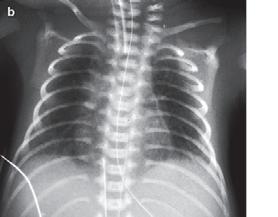

Obr. 1.5b Syndrom dechové tísně u předčasně narozeného novorozence, RTG hrudníku, který byl provedený za 4 hodiny po podání surfaktantu, zlepšení transparence obou plicních polích při klinickém zlepšení stavu [29]

• u 21 % novorozenců s porodní hmotností pod 1000–1500 g

• u 7 % novorozenců s porodní hmotností 1500–1750 g

• RTG hrudníku: kardiomegalie, zvýšené prokrvení plic a edém plic (→ obr. 1.6)

• Echokardiografie: přímé zobrazení PDA a diastolického zpětného průtoku v pulmonální arterii s odhadem velikosti zkratu

Obr. 1.6 RTG hrudníku při perzistujícím ductus arteriosus s kardiomegalií a zmnoženou plicní kresbou, zejména centrálně